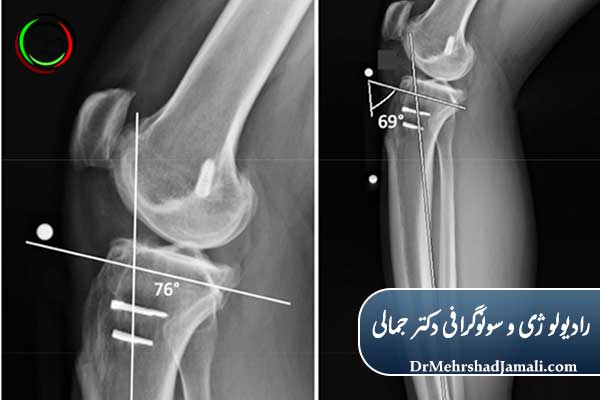

عکس زانو از جلو و کنار (AP & Lateral X-Ray)

رایجترین نوع است که زاویههای مختلف زانو را نشان میدهد و برای بررسی شکستگی، تغییرات مفصلی و آسیب غضروف استفاده میشود.